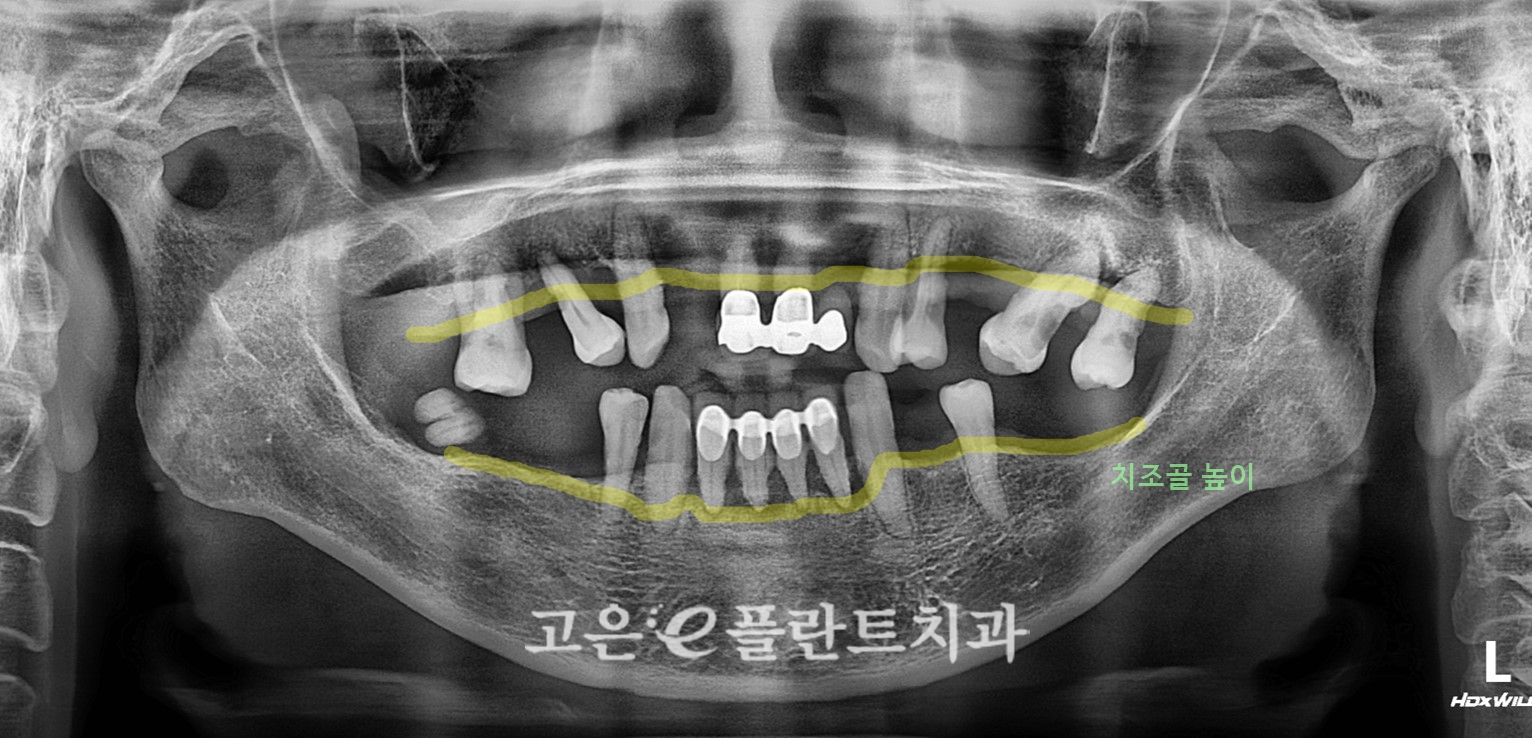

처음 내원하셨을 때,

윗니 앞니 쪽 보철물이 전체적으로 연결된 상태였는데 이미 많이 흔들리고 있었습니다.

겉으로 보기엔 앞니 보철이 조금 흔들리나 보다 하실 수 있지만,

잇몸과 뿌리 쪽을 자세히 보니

잇몸이 많이 내려가 있고, 치아 뿌리가 거의 다 노출되어 있으며

치주염으로 인해 잇몸뼈(치조골)가 상당 부분 녹아 있는 상태였습니다.

아랫니도 크게 다르지 않았습니다.

부분적으로 남아 있던 치아들이 대부분 치주염 말기 단계에 가까워

“어디 하나 튼튼하다”고 말하기 어려운 상황이었죠.